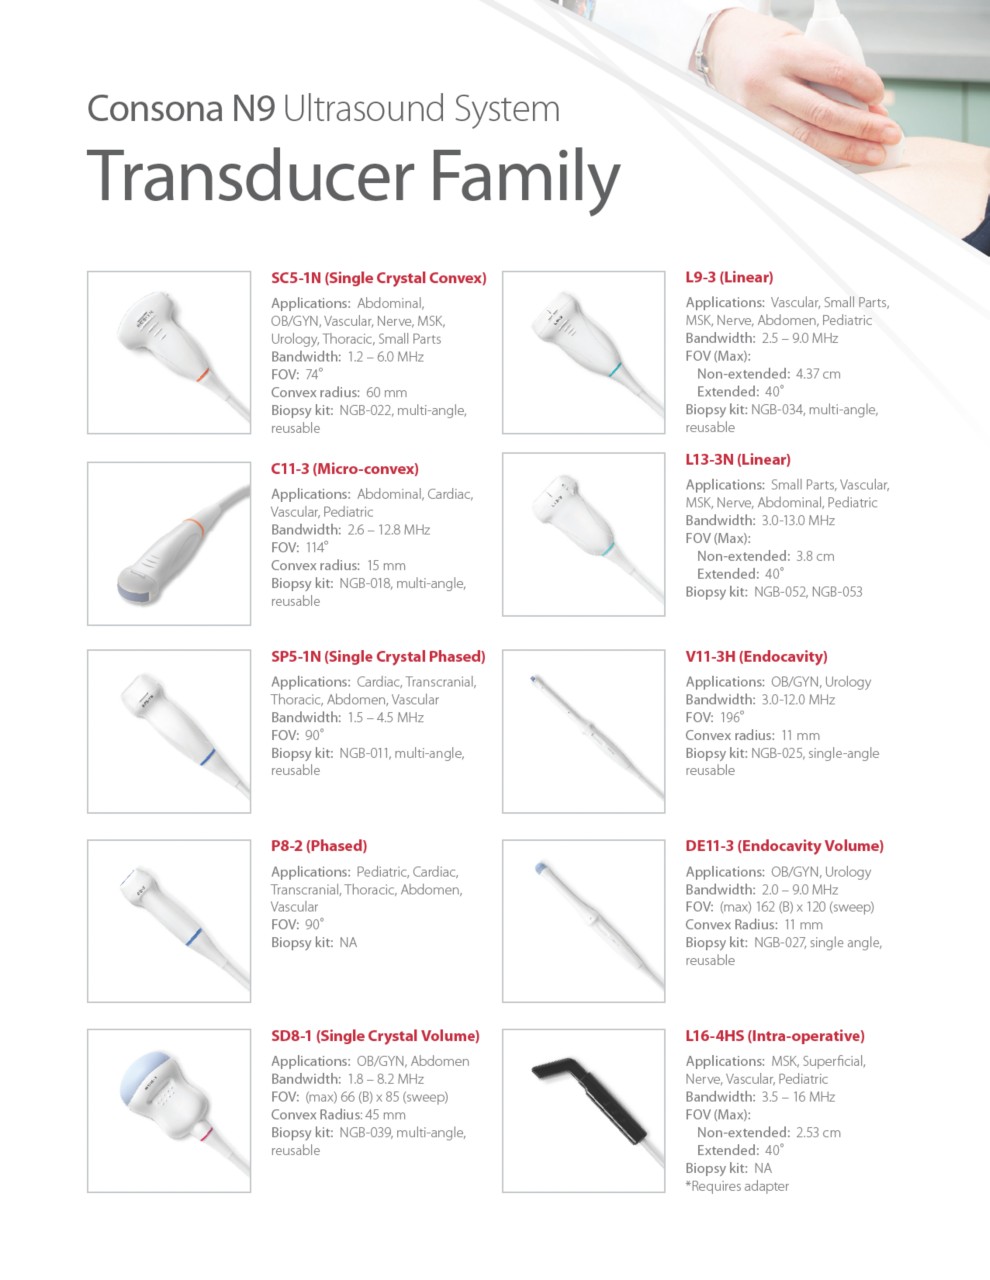

Consona N9

Ultrasound Machine

Women's Health | Radiology | Cardiovascular Imaging